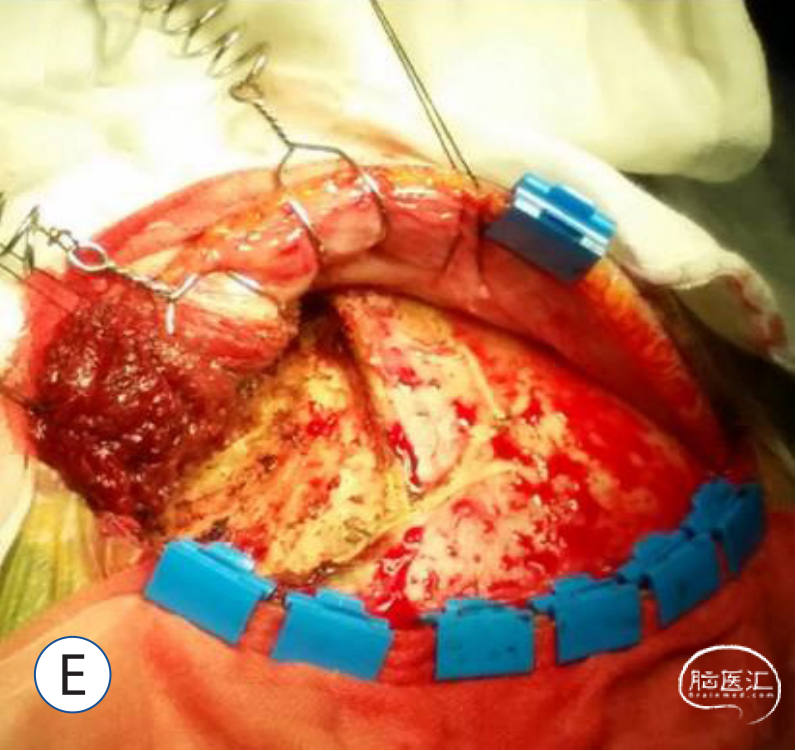

E:使用鱼钩和缝合带牵拉颞肌。

E:切断颞肌的前部和上部。